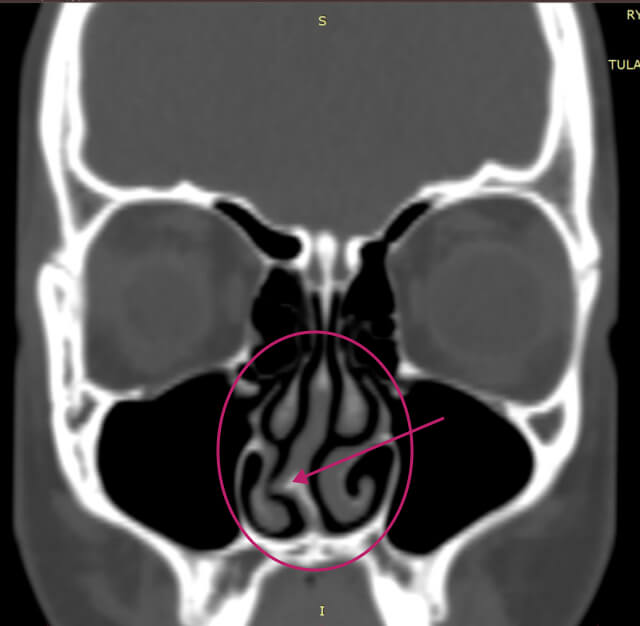

Бүтэц, хэлбэрийн гажигийн жишээ: хамрын таславчийн мурийлт

Харшлын риниттэй өвчтөнүүдэд хамрын таславчийн мурийлт байвал тухайн өвчний явцад сөрөг нөлөө үзүүлэх боломжтой.

Хамрын таславчийн бага зэргийн мурийлт бол хүн амын ихэнхид нь тохиолддог, хэрэв өвчтөнд илэрхий хүндрэл үүсгэхгүй байгаа бол хэвийн гэж үзэж болно. Гэвч хөгжлийн гажиг эсвэл гэмтлийн улмаас үүссэн хамрын таславчийн нилээн их хэмжээний мурийлт нь илүү хүнд үр дагаварт хүргэж болно.

Хамрын таславчийн мурийлт нь хурц хэлбэрийн ринитээс архаг хэлбэрийн ринитэд шилжих хамгийн түгээмэл шалтгаануудын нэг болдог. Үүнээс гадна, иймэрхүү бүтцийн өөрчлөлт нь ургацаг болон уйланхай үүсэхэд нөлөөлж болзошгүй, мөн амьсгалын чадвар буурах, хурхирах, амьсгал түр зогсох (апноэ) зэрэг хүндрэлүүдэд хүргэж болно.